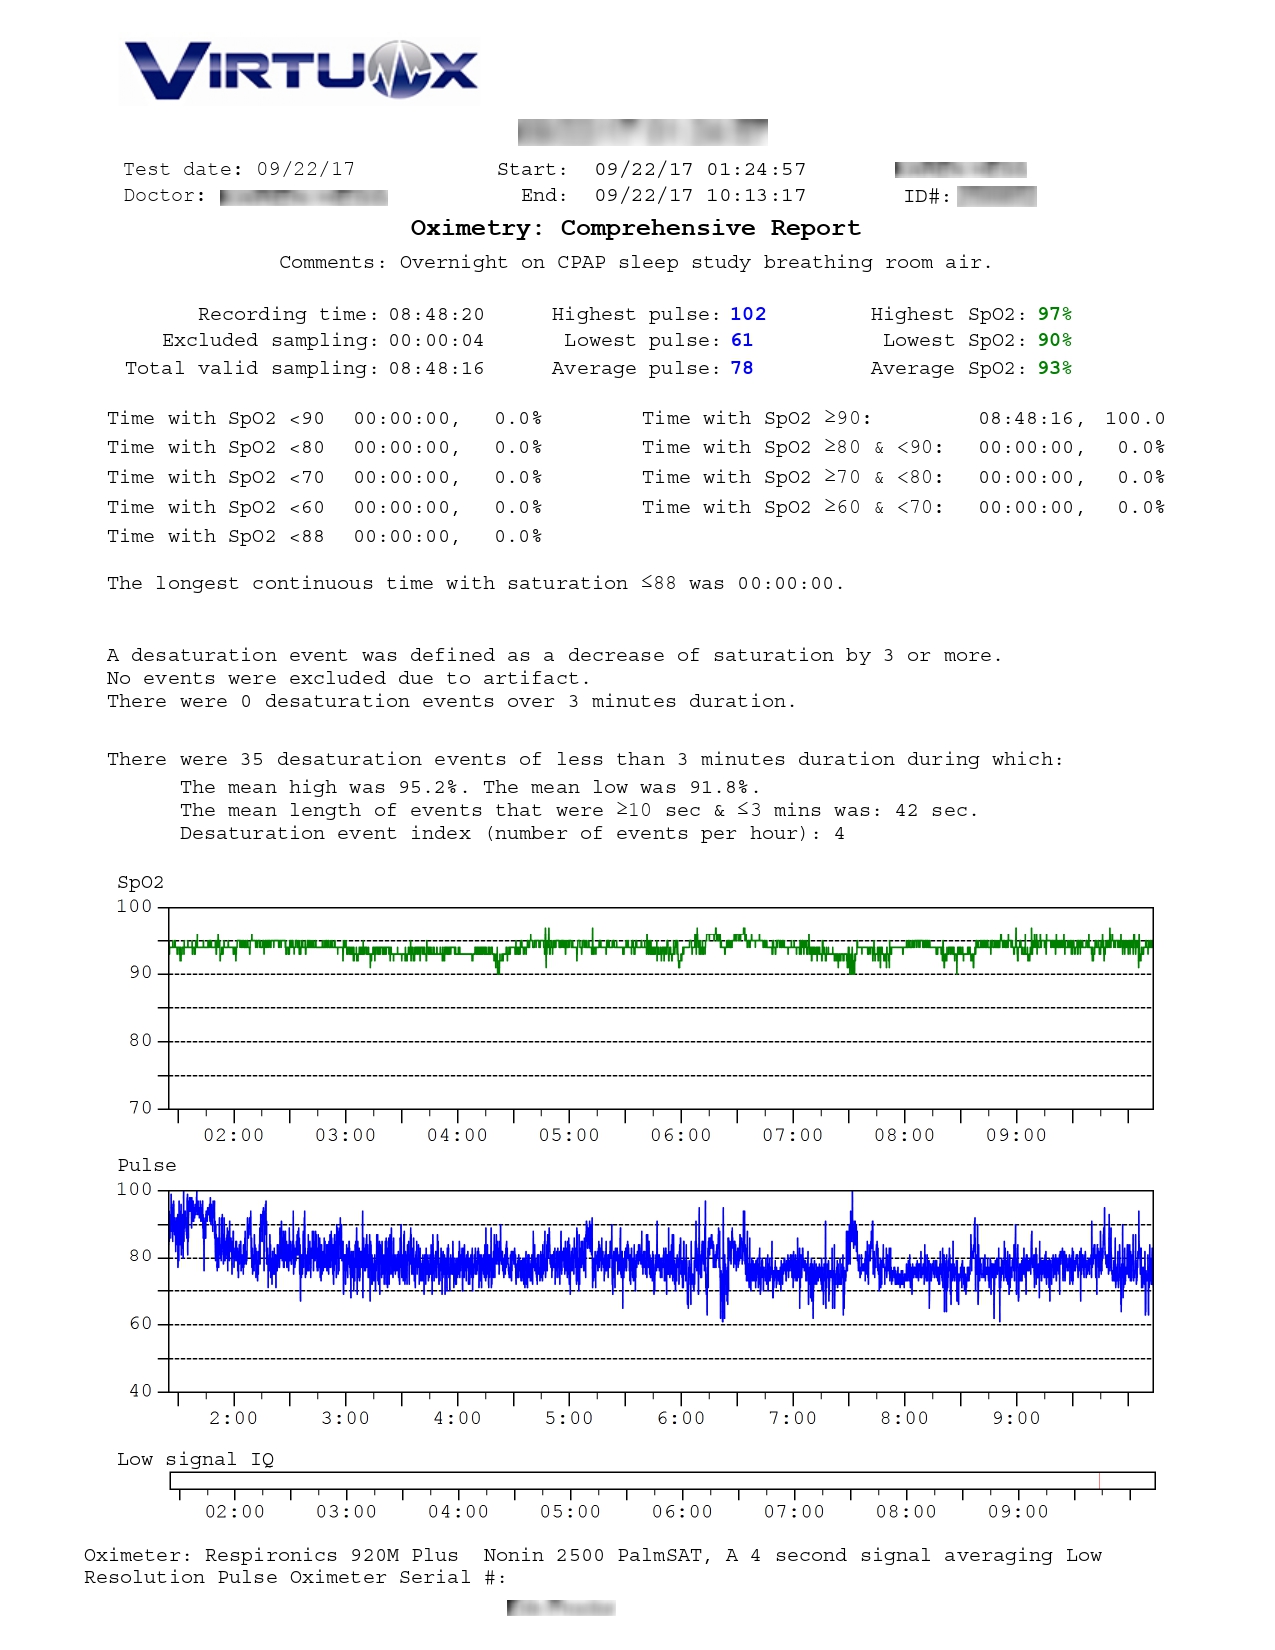

VirtuOx™ offers both a one page summary report and a multiple page detailed report. Both styles are easy to read and include data, as well as graphs.

Hypoxemia can cause serious cardiac arrhythmias

like tachycardia and bradycardia.

With the CardioCHECK enhancement to our

existing overnight pulse oximetry reports,

prescribers can now view the following heart

rate statistics:

- High pulse

- Low pulse

- Average Pulse

- Bradycardia time

- Percent time in Bradycardia

- Tachycardia time

- Percent time in Tachycardia